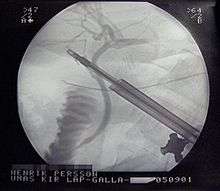

Treatment is usually with laparoscopic gallbladder removal, within 24 hours if possible.[4][9] Taking pictures of the bile ducts during the surgery is recommended.[4] The routine use of antibiotics is controversial.[10][8] They are recommended if surgery cannot occur in a timely manner or if the case is complicated.[8] Stones in the common bile duct can be removed before surgery by ERCP or during surgery.[4] Complications from surgery are rare.[6] In people unable to have surgery, gallbladder drainage may be tried.[8]

For most people with acute cholecystitis, the treatment of choice is surgical removal of the gallbladder, laparoscopic cholecystectomy.[25] Laparoscopic cholecystectomy is performed using several small incisions located at various points across the abdomen. Several studies have demonstrated the superiority of laparoscopic cholecystectomy when compared to open cholecystectomy (using a large incision in the right upper abdomen under the rib cage). People undergoing laparoscopic surgery report less incisional pain postoperatively as well as having fewer long term complications and less disability following the surgery.[26][27] Additionally, laparoscopic surgery is associated with a lower rate of surgical site infection.[28]

During the days prior to laparoscopic surgery, studies showed that outcomes were better following early removal of the gallbladder, preferably within the first week.[29] People receiving early intervention had shorter hospital stays and lower complication rates. In the era of laparoscopic surgery, a similar approach is still advocated. In a 2006 Cochrane review, early laparoscopic cholecystectomy was compared to delayed treatment. In a review early or delayed surgical management there was no difference in terms of negative outcomes including bile duct injury or conversion to open cholecystectomy.[30] However, the early group was found to have shorter hospital stays.[30] For early cholecystectomy, the most common reason for conversion to open surgery is inflammation obscuring Calot's triangle. For delayed surgery, the most common reason was fibrotic adhesions.[30]